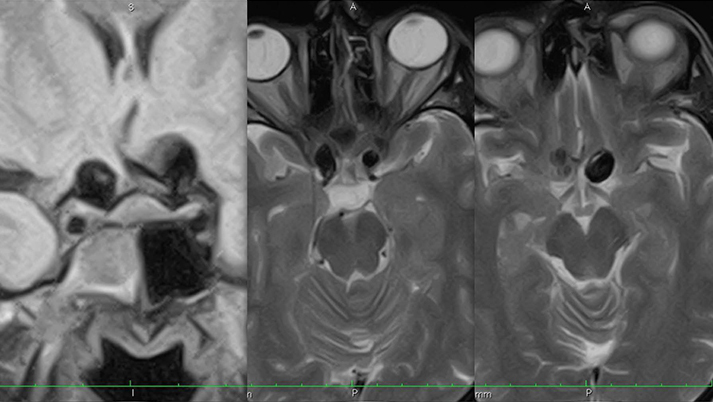

έχουν πυκνή κάλυψη από μέταλλο, με αποτέλεσμα να τροποποιούν την δυναμική της ροής του αίματος κατά μήκος του ανευρυσματικού αυχένος και να προάγουν την ενδο-ανευρυσματική θρόμβωση. Το FDS προοδευτικά ενσωματώνεται στο τοίχωμα του αγγείου μέσω της ανάπτυξης νεο-ενδοθηλίου που έχει ως αποτέλεσμα την πλήρη ανατομική εξάλειψη του ανευρύσματος από την κυκλοφορία. Καθώς ο ανευρυσματικός σάκκος θρομβώνεται, και αργότερα απορροφάται, δευτερογενώς εξαλείφονται τα πιετσικά φαινόμενα (mass effect) στις γειτονικές δομές του εγκεφάλου και αποκαθίσταται η εξω-αγγειακή ανατομία. Το ενδιαφέρον είναι ότι η ροή προς τους φυσιολογικούς κλάδους διατηρείται, όπως και η βατότητα των διατιτραινόντων κλάδων που εκφύονται από το θυγατρικό αγγείο.

FDS - ΚΑΘΥΣΤΕΡΗΜΕΝΗ ΑΙΜΟΡΡΑΓΙΑ (AJNR, Kulcsar 2011)

- Η εκτεταμένη ενδο-ανευρυσματική θρόμβωση μπορεί να έχει ως αποτέλεσμα την καθυστερημένη ρήξη του ανευρύσματος, προκάλεσε απώλεια του ενθουσιασμού και της εμπιστοσύνης στην τεχνολογία των FDs.

RADAR STUDY (ESMINT, 2012)

- Οι καθυστερημένες ρήξεις αφορούν τα μεγάλα ανευρύσματα με μέση διάμετρο 24 χιλ, οπότε μόνο τα μεγάλα και γιγαντιαία ανευρύσματα είνια επιρρεπή σε αυτή την επιπλοκή. Έτσι αναγνωρίζονται ομάδες υψηλού κινδύνου γιά πιθανή καθυστερημένη αιμορραγία σε πολύ μεγάλα και γιγαντιαία ανευρύσματα.